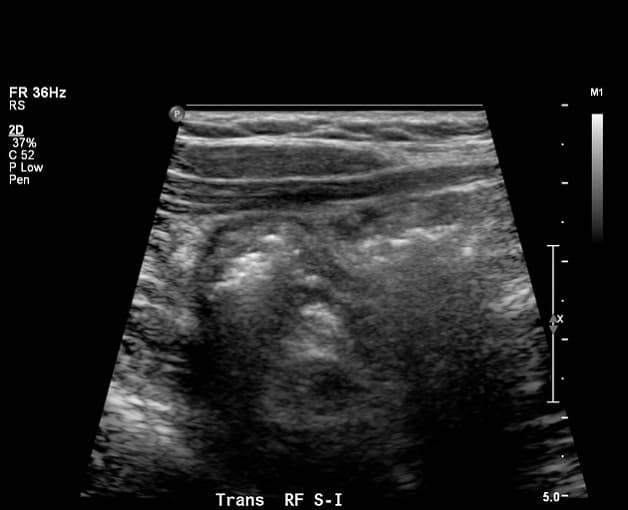

Các bác sĩ sử dụng các xét nghiệm hình ảnh để xác định chẩn đoán bệnh viêm ruột thừa hoặc tìm các nguyên nhân khác gây đau bụng.

– Siêu âm ổ bụng: Trong siêu âm, chuyên gia chăm sóc sức khỏe sử dụng một thiết bị, được gọi là bộ chuyển đổi, phát sóng âm thanh an toàn, không đau từ các cơ quan của bạn để tạo ra hình ảnh về cấu trúc của chúng. Người đó có thể di chuyển đầu dò sang các góc độ khác nhau để kiểm tra các cơ quan khác nhau. Trong siêu âm bụng, chuyên gia chăm sóc sức khỏe thoa một lớp gel lên vùng bụng của bạn và di chuyển đầu dò cầm tay trên da của bạn. Chuyên gia chăm sóc sức khỏe thực hiện quy trình này tại phòng khám bác sĩ, trung tâm ngoại trú hoặc bệnh viện và bạn không cần gây mê. Các chuyên gia chăm sóc sức khỏe sử dụng siêu âm làm xét nghiệm hình ảnh đầu tiên cho khả năng viêm ruột thừa ở trẻ sơ sinh, trẻ em, thanh niên và phụ nữ mang thai.

– Ngoài ra, bác sĩ X quang xem xét các hình ảnh, có thể cho thấy các dấu hiệu của tắc nghẽn trong lòng ruột thừa của bạn và các nguyên nhân khác của đau bụng

Các chuyên gia chăm sóc sức khỏe sử dụng siêu âm làm xét nghiệm hình ảnh đầu tiên cho khả năng viêm ruột thừa ở trẻ sơ sinh, trẻ em, thanh niên và phụ nữ mang thai.